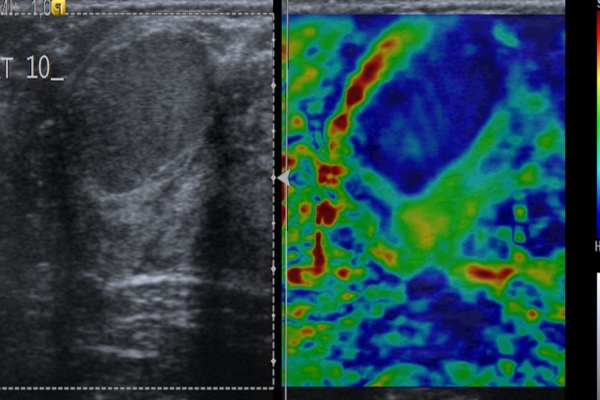

Η ελαστογραφία μαστού είναι μια σύγχρονη υπερηχογραφική μέθοδος που επιτρέπει τη διάκρισητων καλοήθων ογκιδίων από τους κακοήθεις όγκους.

Συνοπτικά ασκείται μια μικρή πίεση στους εντοπισμένους όγκους, μετρώντας την ελαστικότητα τους.

Ο καρκίνος γενικά εμφανίζει μεγαλύτερη σκληρότητα-ελαττωμένη ελαστικότητα σε σχέση με τα καλοήθη ογκίδια και επομένως η ελαστογραφία μπορεί να δώσει τις αναγκαίες πληροφορίες έτσι ώστε να μειώσει τις βιοψίες μαστού μόνο στις απολύτως απαραίτητες.